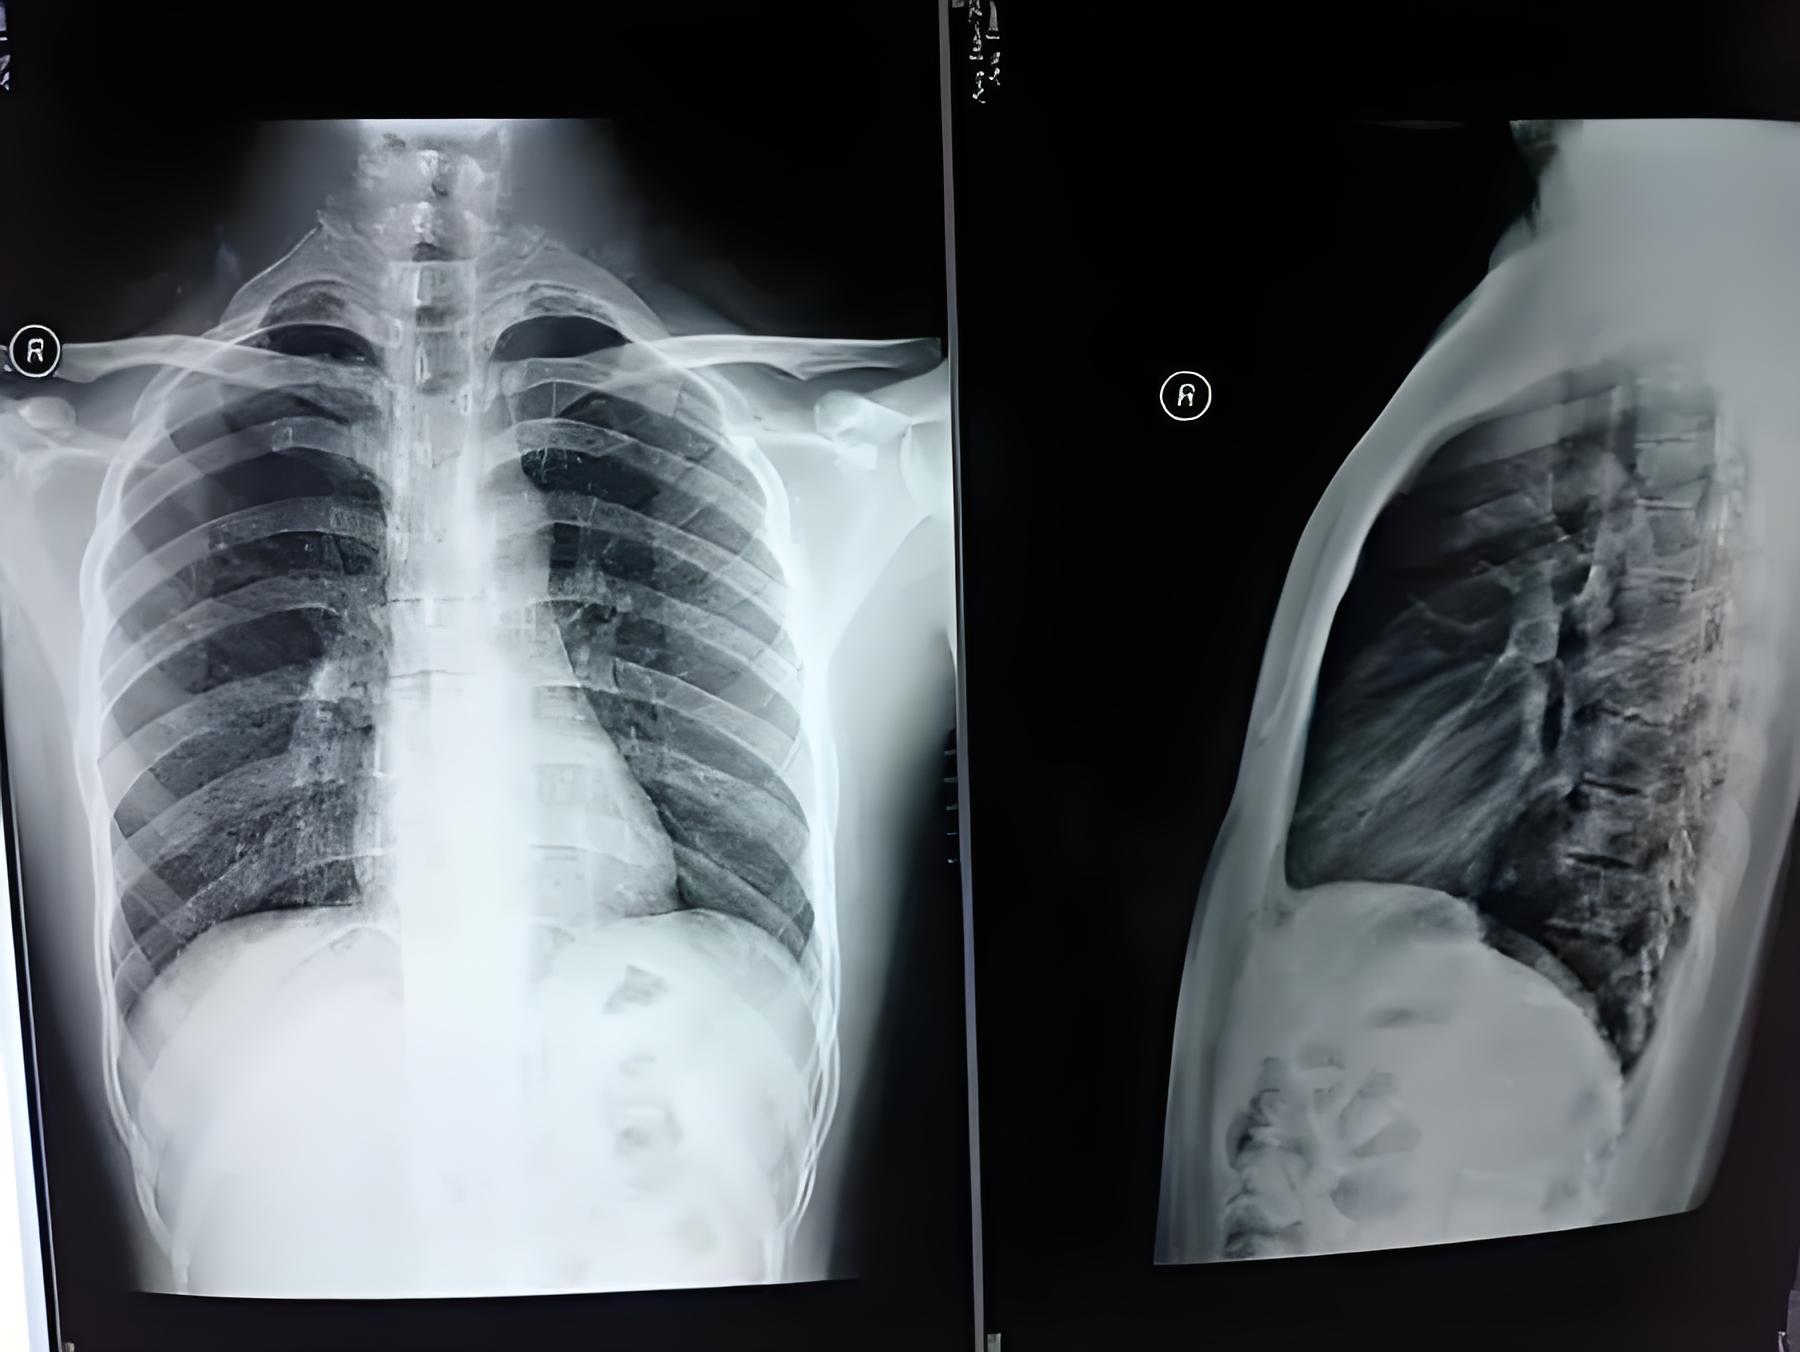

在入职体检中,通常会进行肺结核相关的检查。其中最常见的是胸部X光检查。胸部X光透视可以帮助医生观察肺部情况,是否存在结核病灶。如果X光检查异常,需要进一步进行胸部CT或其他检查来做进一步的评估。